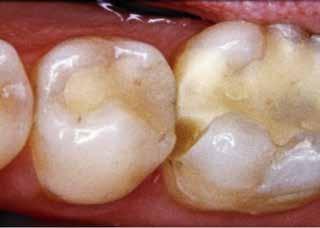

Fig. 3. (A). Histologiske træk ved en veldefineret dyb læsion. (B). Detaljer viser, at bakterierne ikke har nået pulpa. Den tertiære dentin er delvist atubulært, og pulpa har intet inflammatorisk infiltrat. (C). Bakterierne har nået tertiær dentin i den ekstremt dybe carieslæsion. (D). Detalje, der viser, at regionen er delvist nekrotisk og med et underliggende inflammatorisk infiltrat. Hæmatoxylin-eosinfarvning. (Med tilladelse fra (16) og Wiley).

Fig. 3. (A). Histological features of a well-defined deep lesion. (B). Detail shows that the bacteria have not reached the pulp. The tertiary dentine is partly atubular and the pulp has no inflammatory infiltrate. (C). The bacteria have reached tertiary dentine in the extremely deep carious lesion. (D). Detail showing the region to be partly necrotic and with a subjacent inflammatory infiltrate. Hematoxylin-eosin stain. (With permission from (16) and Wiley).

baggrund for henholdsvis den selektive og den gradvise ekskavering (24,25). Forstået på den måde at man på ubehandlede

A C D B 471 2024 128 6

Et relativt nyt studie (16) har sammenholdt disse radiologiske veldefinerede stadier af penetrationsdybde med det pulpale respons vurderet histologisk og har vist, at ved “dybe” carieslæsioner har bakterierne ikke penetreret til pulpa endnu, den tertiære dentin er delvist atubulær, og der ses endnu ikke et inflammatorisk infiltrat i pulpa (Fig. 3A og B). Hvorimod ”ekstremt” dybe carieslæsioner typisk har bakterier, der har nået den tertiære dentin eller er i direkte kontakt til pulpa (Fig. 3C, D). På dette tidspunkt vil et inflammatorisk infiltrat kunne ses i pulpa, og pulpal skade er tydelig i form af nekrotiske områder (Fig. 3D). Disse fund er i overensstemmelse med et Brusk i pulpa